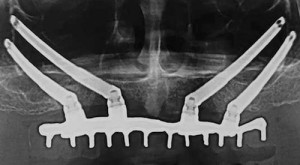

Authors: P. Felice, C. Barausse, R. Davó, R. Pistilli, C. Marti-Pages, A. Ferrer-Fuertes, A. Ferri, M. Esposito

PURPOSE. To compare the clinical outcomes of immediately loaded cross-arch maxillary prostheses supported by zygomatic implants versus conventional implants...